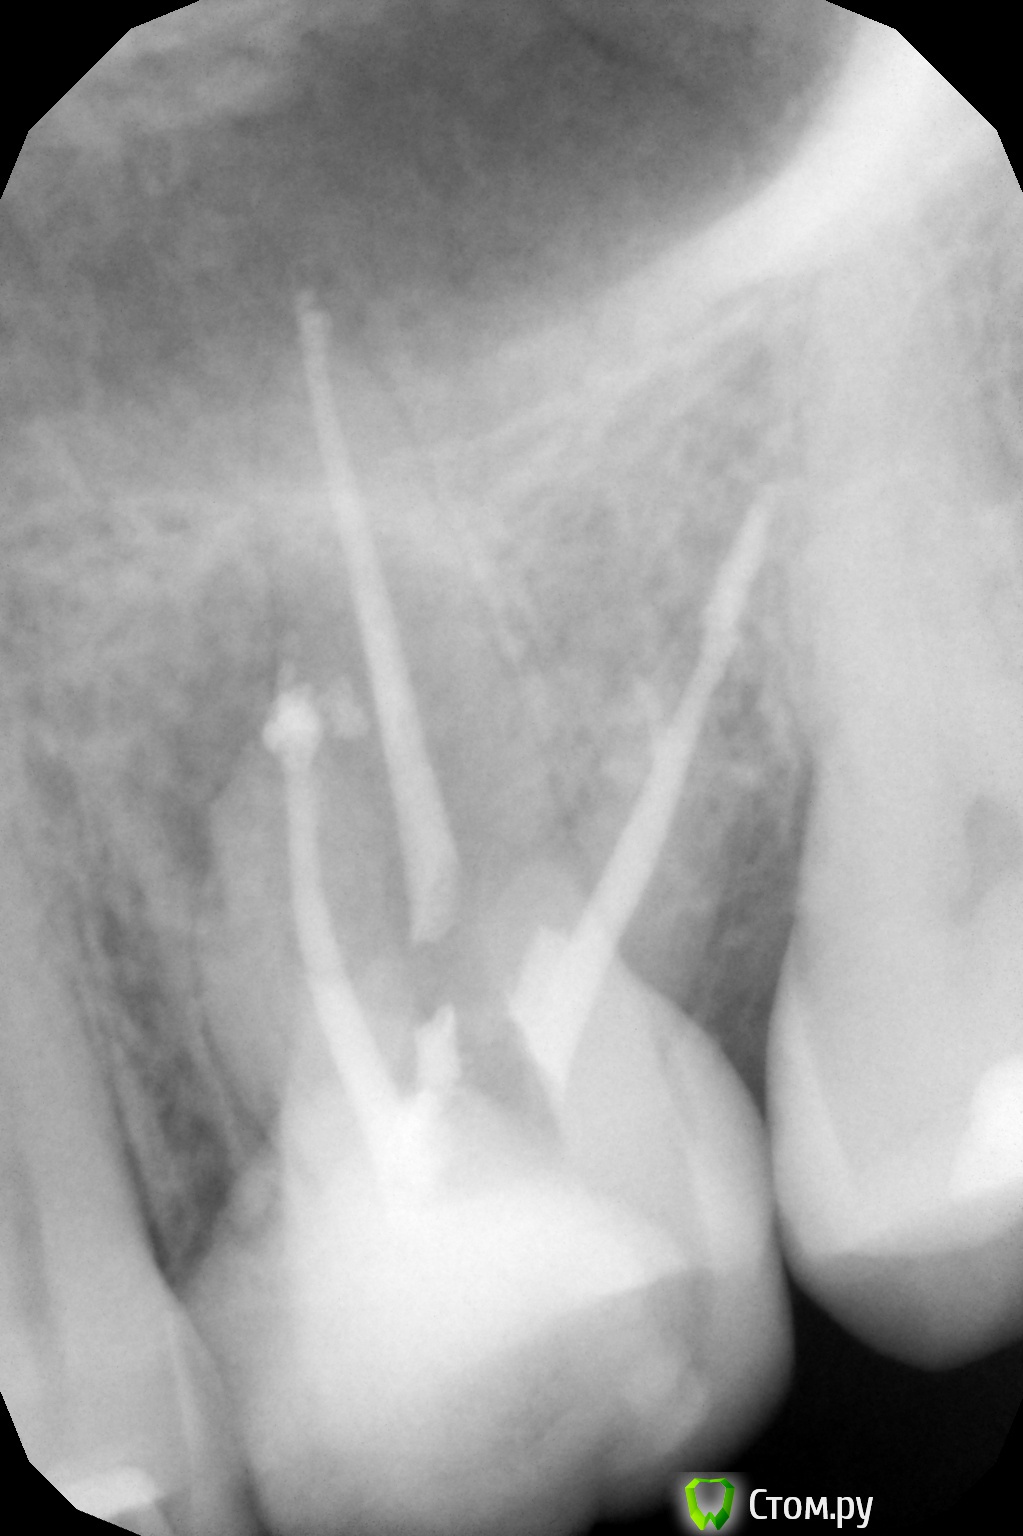

oksanab Опубликовано 9 октября, 2014 Поделиться Опубликовано 9 октября, 2014 (изменено) мне лечили 26-й зуб и медсестра озвучила, что нет 40-го и 38-го штифта .В итоге врач поставил просто эндометазон без гуттаперчей. Это я узнала, когда мне зуб вскрыли и стали перепломбировывать один канал, ввиду того, что паста там была не застывшая, мягкая. Является ли это ошибкой терапевта, когда паста мягкая в канале? . Плохо ли, когда эндометазон без гуттаперчи(судя по всему не было 40-го )? И почему ,как вы думаете, уже другой терапевт перелечила только центральный канал и не тронула остальные, хотя я просила об этом(потому что ортопед попросил). Она только загерметизировала остальные два канала(возможно апексом, не знаю, а вот центральный канал апексом верхушку корня залила). Достаточно ли этого, или лучше все-таки перепломбировать и два остальных канала?(в одном из них судя по всему перфорация, на другом - лекарство выведено за канал ,а может эндометазон за канал с лечебной целью выведен.... В выписке предыдущий врач не отметил, какое конкретно лекарство за каналом было выведено. Прилагаю снимки, на первом три канала 12 лет назад, на втором и третьем - перелечивание и пломбировка эндометазоном всех трех каналов(просто два снимка в разных клиниках ,но суть одна), да еще и скол зуба появился небольшой(ортопеды говорят, поправимо), и на третьем снимке перепломбировали только центральный канал. Нормально ли перепломбировали хоть средний канал? на мой взгляд как-то верхушка его странно расширилась, была поуже на 2-м и 3-м снимке(пломбировали методом латеральной конденсации). Подскажите пожалуйста, что думаете? Изменено 9 октября, 2014 пользователем oksanab Ссылка на комментарий

Cleric Опубликовано 9 октября, 2014 Поделиться Опубликовано 9 октября, 2014 (изменено) В вашем зубе "пропущен" ещё один канал в переднем щечном корне. Зуб на адекватное перелечивание. В этом зубе минимум 4 канала. Изменено 9 октября, 2014 пользователем Cleric Ссылка на комментарий

Паращук Роман Опубликовано 10 октября, 2014 Поделиться Опубликовано 10 октября, 2014 (изменено) Сравните снимки.Ты видишь суслика? Нет? И я нет,а он есть! (с)ПиСи Пропущенный канал,перфорация,мат-ял за верхушкой. Зуб уже визу в плевательницу открыл.http://s020.radikal.ru/i708/1410/b7/ad9c402a2f4c.jpghttp://s43.radikal.ru/i099/1410/5f/23581663b182.jpg Изменено 10 октября, 2014 пользователем Паращук Роман Ссылка на комментарий